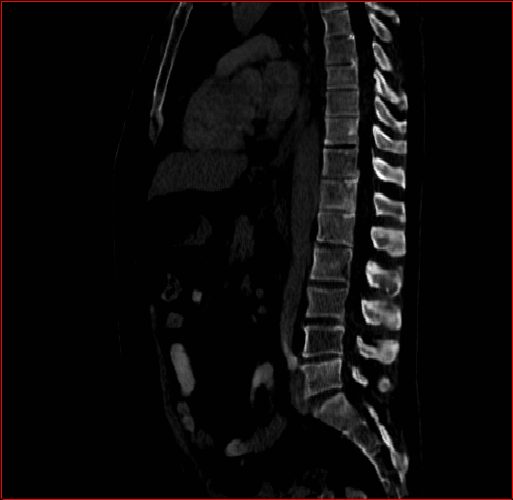

Figure 2: Qualitative comparison across axial (top row), sagittal (middle row), and coronal (bottom row) views. Columns correspond to different methods. MAISI-DDPM and MAISI-v2 in this figure are unconditional synthesis which do not use ControlNet or segmentation maps.

Qualitative Evaluation:

Figure 2 presents representative slices from the axial, sagittal, and coronal planes. GenerateCT (hamamci2024generatect) is a 2D model, so it lacks inter-slice consistency, leading to poor image quality in the sagittal and coronal views. MedSyn (xu2024medsyn) produces noticeably blurry results with mosaic-like artifacts, such as region inside the red box. HA-GAN (sun2022hierarchical) generates visually sharp images but with mosaic-like artifacts, such as region inside the red box. Also, its voxel spacing is not available, which limits its applicability in real-world medical imaging tasks. Moreover, all three methods are restricted to synthesizing small anatomical regions. In contrast, both MAISI and MAISI-v2 are capable of generating high-quality 3D volumes that span larger body regions while preserving fine anatomical details and realistic structure.